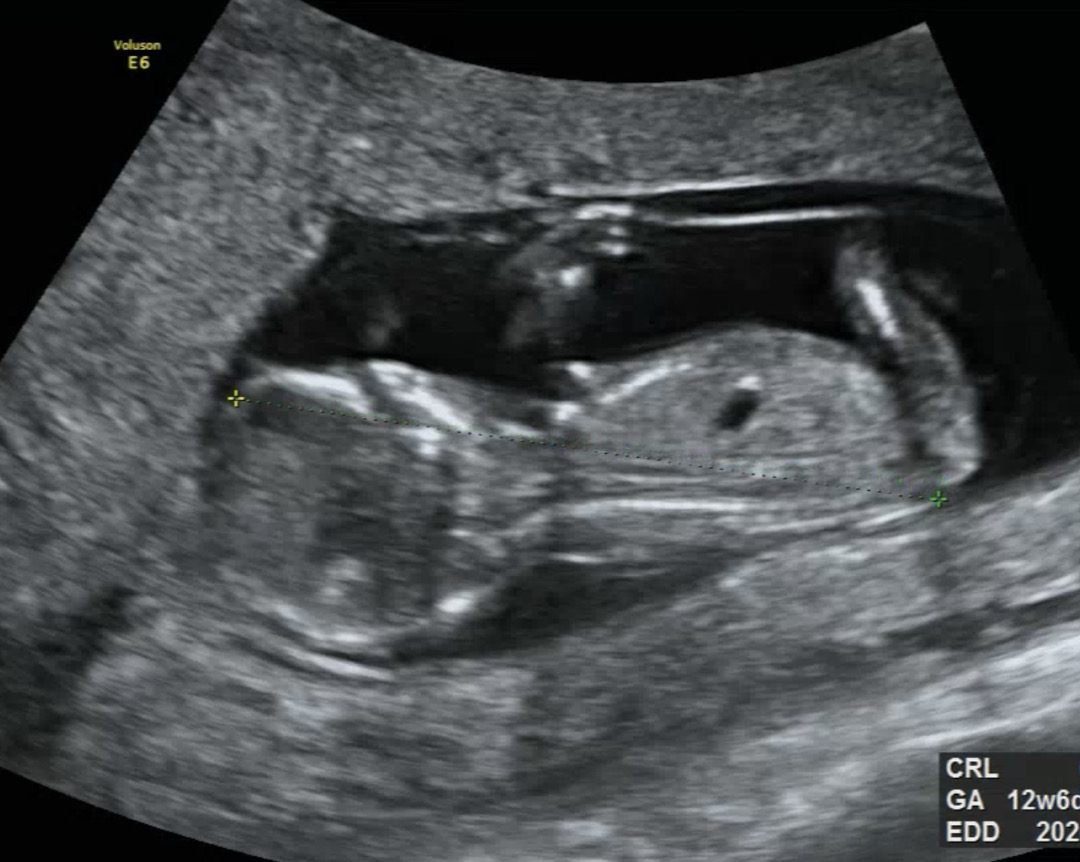

12주차 각도법!!! 입체 + 일반 초음파 올려보아요👍🏻

각도법 선배님들 ㅎㅎ 혹시 어떤 성별인지 감이 오실까요??? 아들이든 딸이든 다 좋아요>< 소중한 시간 내셔서 우리 하모 성별 봐주심에 감사합니다^^